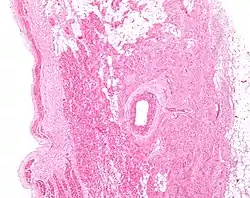

![]() 中央偏右处便是窦房结 | |